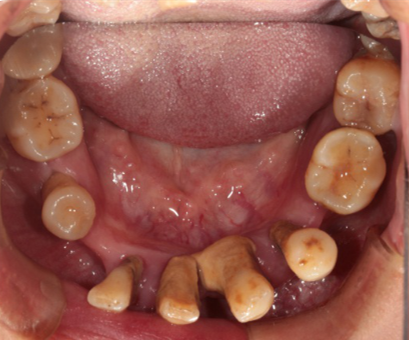

Intraoral Examination(A zone=Right upper jaw、B zone=Left upper jaw、C zone=Left lower jaw、D zone=Right lower jaw)

Poor oral hygiene, accumulation of calculus, three-degree loosening of the entire mouth

Periodontitis causes severe absorption of the upper and lower jaws

A zone A4-A6、B zone B2、C zone C2-C4、D zone D2-D3 lost

A zone A1-A3、A7、B zone B1、B5-B7、C zone C1、C5-C7、D zone D1、D4-D8 all with III°loosen

Photos of preliminary oral diagnosis